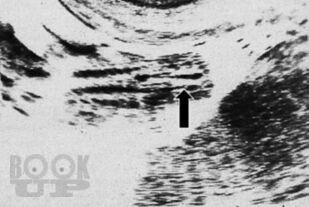

Синдром миелодисплазии у детей (клиника, диагностика, лечение)

Эволюция хирургических методов лечения spina bifi da и ее осложнений позволила по-новому взглянуть на проблему. Многообещающие результаты определили новую стратегию лечения спинальных пациентов. Разработка современных методов исследования, расширение показаний к нейрохирургическим и урологическим вмешательствам, применение современных лекарств, новых методов физиотерапии дали надежду врачам, пациентам и их родителям.

Основная цель этого руководства — поиск путей предотвращения развития обструктивной уропатии верхних мочевых путей и хронической болезни почек — важнейших проблем детской урологии и нефрологии.

Представленное руководство обобщает 30-летний опыт лечения пациентов с миелодисплазией (более 1500 детей), страдающих недержанием мочи и кала, двигательными расстройствами, инфекцией мочевыводящих путей и хронической болезнью почек.